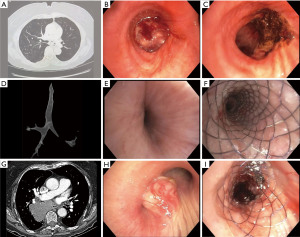

Tumors causing CAO are primarily described by their location in relation to the lumen of the airway: endoluminal, extrinsic, or mixed (Figure 1). Other key factors to consider when classifying CAO are location and degree of stenosis. Together, these three characteristics contribute to symptomatology, define treatment options, and predict treatment outcomes. While endoluminal tumors typically require debulking, extrinsic compression of the airway can be treated with dilation and potentially stenting. Treatment of obstructions with both endo- and extraluminal components utilizes a multi-modality approach (Figure 2).

Figure 2 Types of airway obstruction pre- and post-intervention: (A) endoluminal tumor in the left mainstem bronchus seen on chest CT and (B) bronchoscopy; (C) the tumor was removed with an electrocautery snare and the tumor base was treated with APC; (D) significant LMS bronchus narrowing as seen on chest CT airway reconstruction; (E) extraluminal obstruction of the LMS as seen during bronchoscopy; (F) improvement in LMS bronchus diameter after endobronchial stent placement and balloon dilation; (G) right mainstem and bronchus intermedius narrowing as seen on chest CT; (H) obstruction secondary to endobronchial squamous cell carcinoma and extrinsic compression from the subcarinal lymphadenopathy and right lower lobe mass; (I) APC was used for coagulation and tumor ablation followed by balloon dilation and endobronchial stent placement. CT, computed tomography; APC, argon plasma coagulation; LMS, left mainstem.

Malignant CAO causing symptoms or loss of greater than 50% of airway patency is usually an indication for therapeutic bronchoscopy (37), but a more complete diagnostic evaluation can be obtained prior to pursuing therapeutic interventions in patients that are stable. A variety of bronchoscopic modalities are available for management of MCAO and it is helpful to categorize by those with immediate versus delayed effects and thermal versus non-thermal therapies, as patient-specific scenarios will dictate which are necessary and feasible. Tools are often used in combination and will be briefly discussed in the following sections (Figure 5).